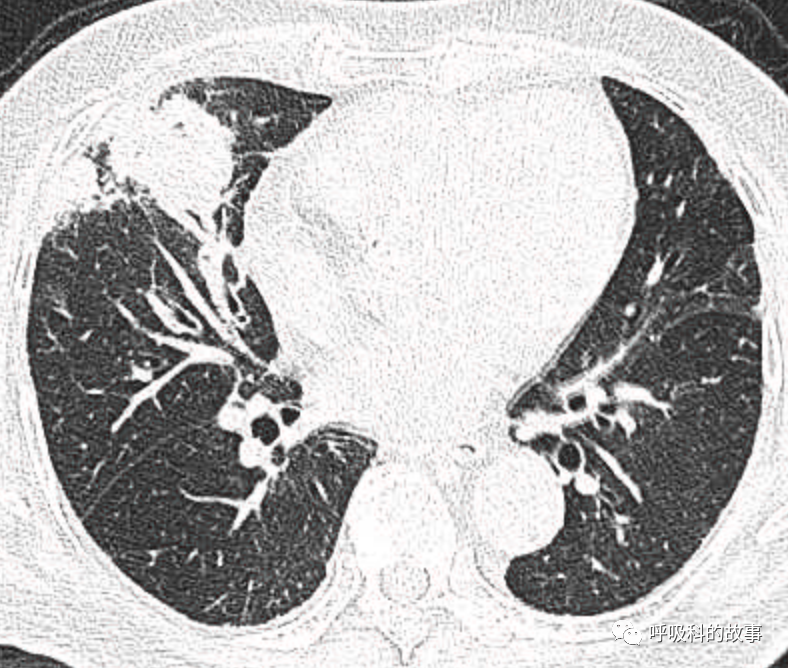

可是就在今年初,患者曾住在某院某科室,因为其他内科疾病住院。当时肺部CT也发现了在右中叶内侧段的高密度实变影,由于影像很类似肺炎,因此当成肺炎治疗。

图12-14:该患者各个角度的影像图像

(上下滑动查看全部图片)